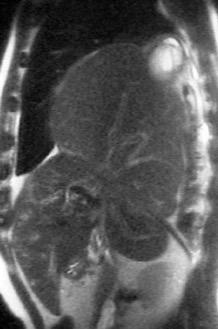

Hallazgos en RM .

Buena en casos dudosos

Cortes sagitales y coronales: Interrupción de la línea diafragmática

Paciente que ingresa con síntomas de colecistitis aguda. Antecedentes de trauma importante muchos años antes

Zhao L et al. Delayed traumatic diaphragmatic rupture: diagnosis and surgical treatment. © Journal of Thoracic Disease.

J Thorac Dis 2021

Asas

Líquido pericolecistítico

V. biliar con cálculos

Diafragma